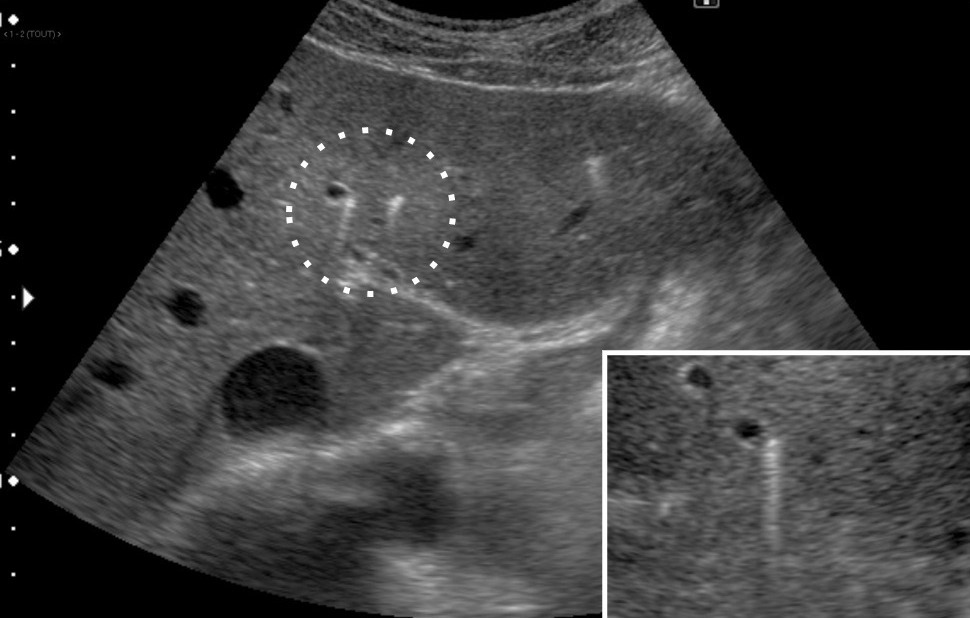

Échographie hépatique : examen clé du diagnostic

L’échographie hépatique est l’examen clé pour le diagnostic de syndrome LPAC. Celle-ci met typiquement en évidence les signes d’une microlithiase intrahépatique sous la forme d’images en « queue de comète » (échos de répétition liés à la vibration des microcristaux sous le faisceau d’ultrasons), de micro-­spots ou de « boue biliaire » (sludge) le long des canaux intrahépatiques (fig. 1A). Ces signes sont parfois difficilement identifiables, notamment en situation non sensibilisée et pour un opérateur non entraîné. Le principal diagnostic différentiel est représenté par les microhamartomes (ou complexes de von Meyenburg) qui peuvent parfois se présenter sous la forme d’artéfacts en queue de comète.9 Une échographie normale standard n’élimine pas le diag­nostic et il peut être nécessaire de répéter l’examen par un radiologue expérimenté et formé à la sémio­logie du syndrome LPAC. Moins fréquemment (5 à 10 % des cas), le syndrome LPAC peut se présenter sous la forme de vrais calculs (macrolithiases) intra- ou extrahépatiques (fig. 1B).4 Une lithiase vésiculaire n’est observée que chez un tiers des patients atteints de syndrome LPAC.